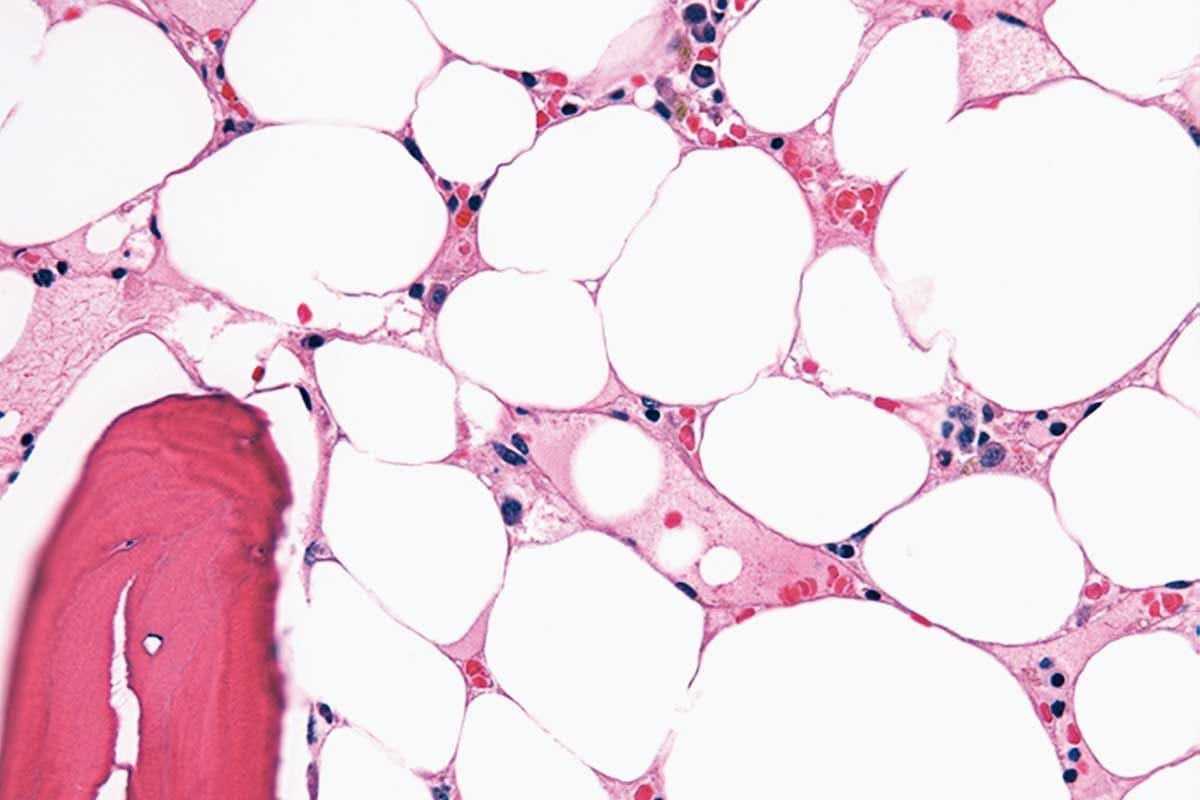

Sickle Cell Disease (SCD) is a genetic disorder that affects red blood cells. It changes how these cells carry oxygen. This is because of a problem with the hemoglobin protein in the cells.

SCD comes from a mutation in the HBB gene. This gene is important for making hemoglobin. The mutation leads to sickle hemoglobin, or HbS, which makes red blood cells sickle-shaped and fragile.

This mutation is a single change in the HBB gene. It swaps glutamic acid for valine at the sixth position of the beta-globin chain. This causes hemoglobin to clump together when there’s less oxygen. This is why red blood cells become misshapen.